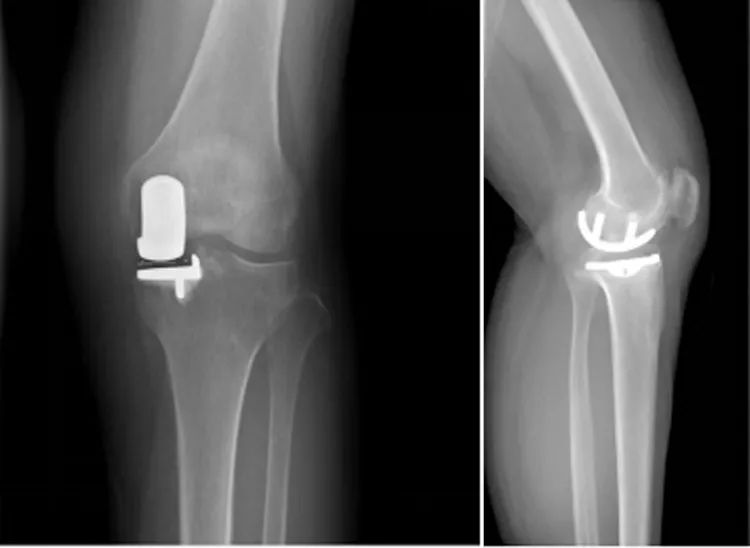

膝关节单髁置换术(unicompartmental knee arthroplasty,UKA)是相对人工全膝关节置换术(total knee arthroplasty,TKA)而言的一种新型微创手术,它们同时诞生于20世纪70年代,但早期 UKA 技术不成熟,存在衬垫磨损、假体脱位等并发症,导致假体生存率低,因此与TKA相比其临床应用较少。近年来,随着手术技术的进步、方案的优化以及假体设计的改善,UKA 术后并发症发生率降低、假体生存率提高,手术指征扩大,越来越多用于临床治疗膝关节单间室骨关节炎。

图片来源:北京德尔康尼骨科医院